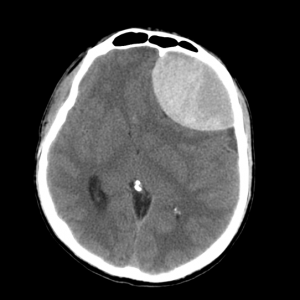

Эпидуральная гематома — отграниченное скопление крови над твердой оболочкой мозга. Различают субтенториальные гематомы, располагающиеся ниже намета мозжечка, и супратенториальные - выше намета мозжечка. Источник кровотечения при эпидуральных гематомах - оболочечные артерии. Основная причина возникновения таких гематом - перелом костей черепа.

Как выглядит субдуральная гематома на снимках КТ? Эпидуральная гематома на КТ имеет форму двояковыпуклой линзы (внутренний контур которой соответствует отслоенной мозговой оболочке), прилежащей к внутренней поверхности кости. В некоторых случаях можно увидеть перелом кости в области дна гематомы. Характерный КТ-признак эпидуральной гематомы — ликворные «стрелки» у углов гематомы (небольшие субдуральные гигромы по краям гематомы, возникающие из-за разрыва арахноидальной облочки и перехода ликвора из арахноидальной полости в субдуральное пространство, а также возможны включения костной плотности (отломки внутренней пластинки). Структура эпидуральных гематом чаще всего однородная, реже неоднородная, в некоторых случаях внутри черепа может визуализироваться газ.

![image013]()

КТ при эпидуральной гематоме. Видно скопление крови в левой лобной области с выраженным объемным воздействием на оболочки и вещество мозга.